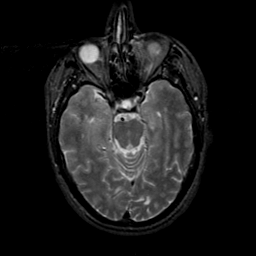

MR Study #21, November 3, 1991 -- Slice #18